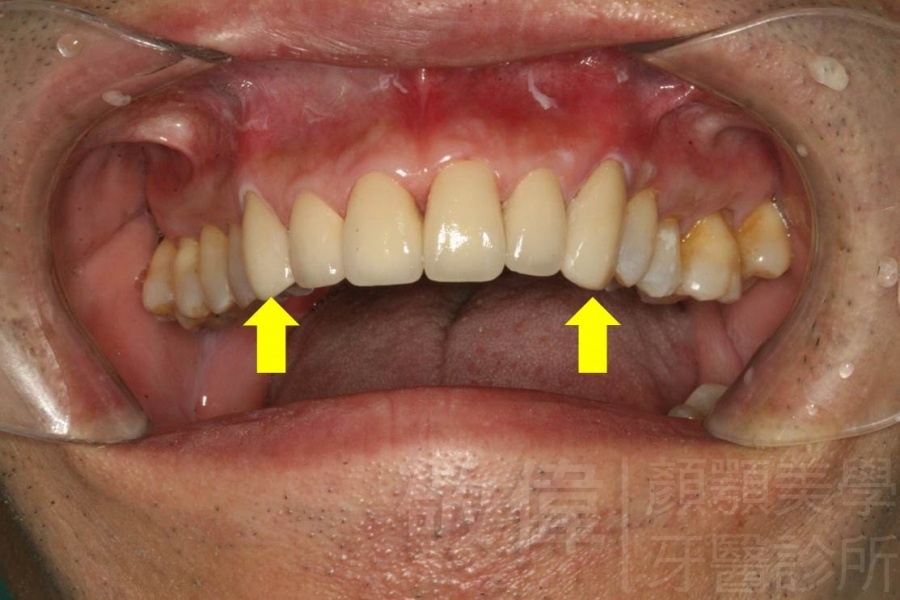

| 8 | 前牙美容 | 快速矯正之美容晶瓷貼片及晶鑽瓷冠 | ||